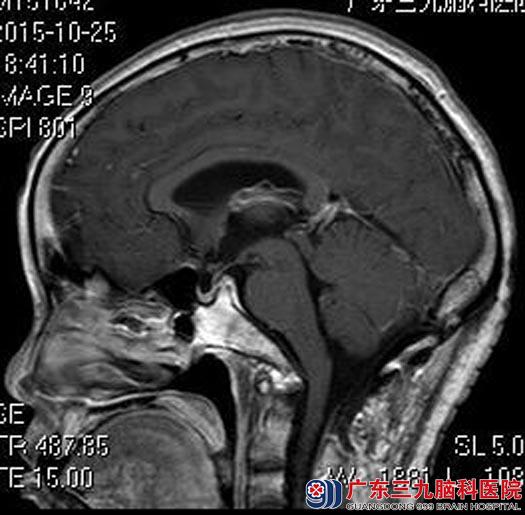

进一步头颅MR检查提示:四脑室下方及枕大孔区示一不规则团块状占位性病变,大小约4.5cm×2.8cm×3.0cm,病变向下突入枕大孔,脑干及小脑受压,考虑室管膜瘤可能。

详细了解治疗方案后,黄女士决定行手术治疗。由鲁明主任主刀在全麻下行四脑室、延髓背侧及枕骨大孔区占位病变切除术,显微镜下见枕骨大孔区及延髓背侧灰褐色肿瘤组织,质软,近小脑下后动脉分支供血,血管丰富,从枕骨大孔区分离肿瘤组织,再延髓背侧逐渐分离,该处为肿瘤起源,分块切除肿瘤,手术过程顺利。

术后,黄女士的饮水呛咳症状好转,无吞咽困难、声音嘶哑等后组颅神经损害症状,已满意出院。术后病理结果:室管膜瘤。